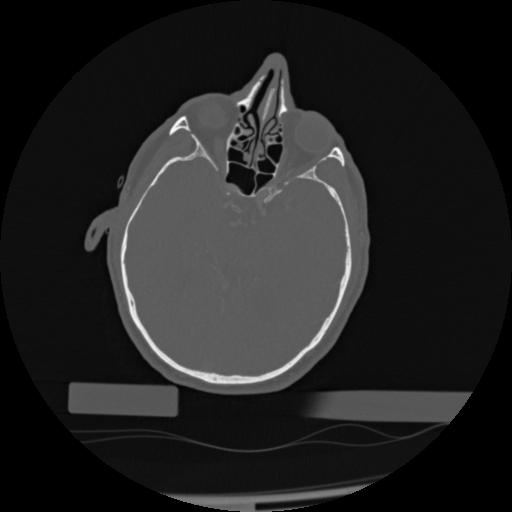

22 ANGIO,CE,Vol,0.5,ANGIO,,